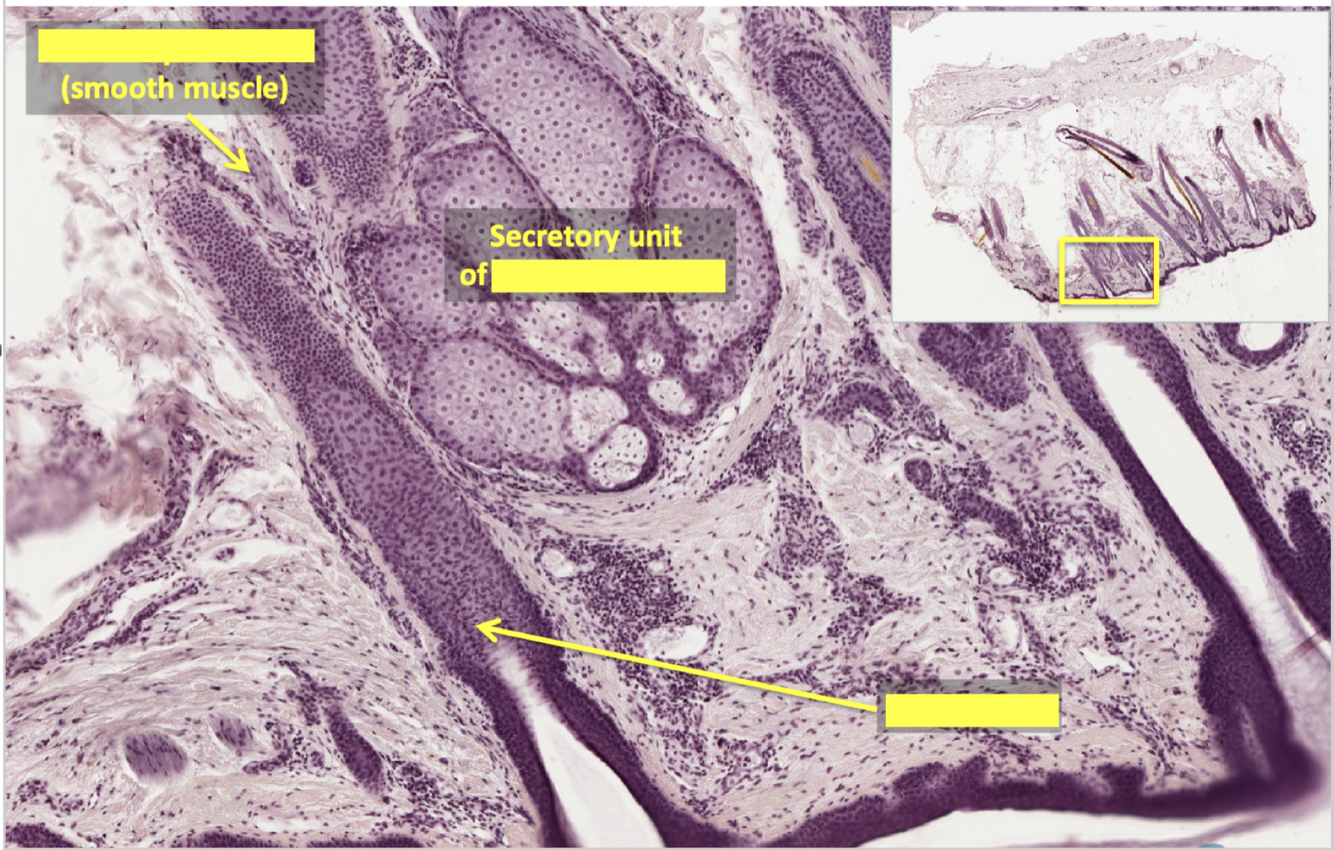

what type of muscle is arrector pili muscle